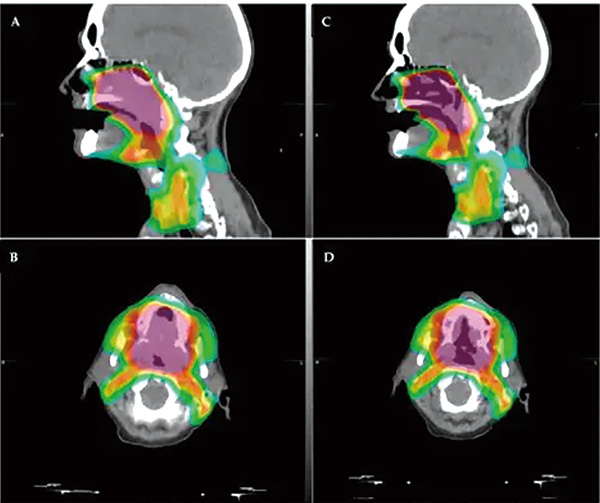

为了评估IMRT的头颈癌患者中放疗与嗅觉功能的相关性,包括嗅觉功能随时间的变化,该项非随机化临床试验招募了2021年1月1日至2023年12月1日组织学确诊并接受IMRT治疗的头颈癌患者。计划接受放疗的患者在多个时间节点接受TWSIT量表的嗅觉功能评估。鼻腔内镜用于排除混杂性的鼻腔疾病(如严重鼻中隔偏移、慢性鼻窦炎、头部外伤或头部放疗史)。主要终点为嗅觉评分与嗅觉区辐射剂量间的相关性。

总体来看,放疗后嗅觉功能评分下降,部分患者在随访期间有部分恢复。小剂量放疗的患者通常保持稳定的嗅觉功能。放疗剂量与嗅觉功能障碍中度正相关。放疗剂量每增加1 Gy,TWSIT评分下降0.128(0.083~0.173)。受试者工作特征分析确定,22 Gy为估算嗅觉障碍的潜在阈值,此时曲线下面积为0.74(95%CI 0.52~0.96,P=0.03),敏感性为64%,特异性为92%。

在11例出现嗅觉功能障碍的患者中,5例的放疗剂量≤22 Gy,6例的剂量较大。多变量分析显示,嗅觉区域平均放疗剂量超过22 Gy是唯一的独立风险因素(OR=20.65,95%CI 2.60~164.35)。部分接受大剂量放疗的患者出现长达1年的持续性的嗅觉功能障碍。根据敏感性和特异性,嗅球部位放疗剂量≤22 Gy或有超过90%的概率避免嗅觉功能障碍。

研究者表示,估计模型进一步显示,超过22 Gy剂量后发生功能障碍的概率会大幅上升,这些发现强调了在放疗计划中仔细评估嗅觉区域放疗剂量和范围的必要性,以防止长期的嗅觉功能障碍。由于放疗技术、辐射剂量和场域、研究设计、嗅觉评估方法以及评估时间的异质性,放疗后嗅觉恢复的潜力仍不确定。